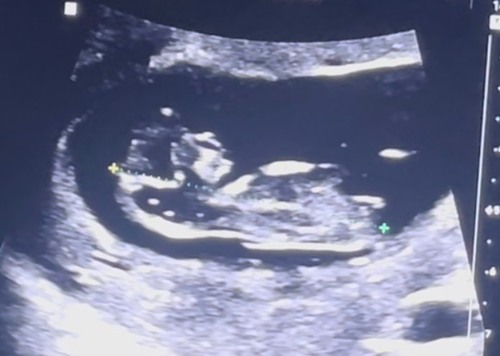

Kan iemand hier al wat uit halen… was hier wel pas 10+3 🙈

Nee, dan ben je te vroeg. Nub kan pas tussen 12-14 weken worden gecheckt.

10.5, kan iemand hier wat van maken?? 😇